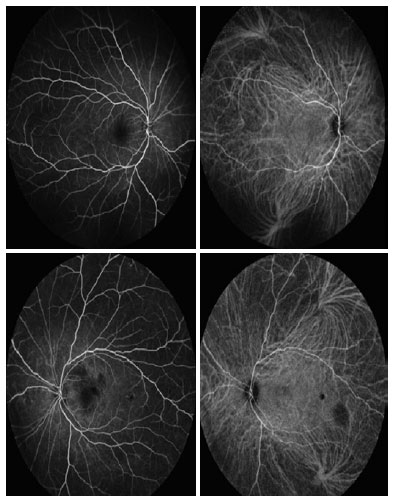

After 2 months, the patient returned for a multimodal study of the retina, which revealed bilateral foveal atrophy of the entire retina and significant temporal inner retinal thinning in the left eye (Figures 2, 3 and 4). It was not possible to perform the multimodal analysis at the onset of the ocular condition as the patient was hospitalized in an intensive care unit in a serious condition, which made her displacement impossible. After 4 months, the patient’s best-corrected visual acuity was 20/50 in the right eye and 20/200 in the left eye. At this time point, no changes were observed on biomicroscopy, while the fundoscopy revealed mild optic disc pallor, preserved vessels without hemorrhage, dry macula, heterogeneous retina color, and clear vitreous body.

10-fig02.jpg)

10-fig03.jpg)

10-fig04.jpg)